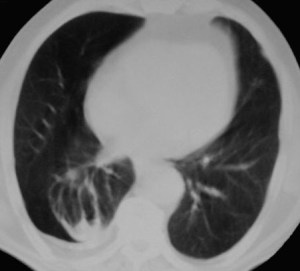

SIGNO DEL CASQUETE APICAL IZQUIERDO

La aparición de una densidad en el ápex pulmonar izquierdo, de borde inferior cóncavo y bien delimitado (casquete apical) en un paciente con traumatismo torácico, debe hacernos sospechar la existencia de una rotura aórtica.

Deben excluirse otras causas de casquete apical, especialmente las lesiones residuales tuberculosas, que suelen acompañarse de otros hallazgos como tractos fibrosos pleuro-parenquimatosos, pérdida de volumen en el lóbulo superior, granulomas, etc.

Mostramos un caso de rotura aórtica por accidente de moto. En este paciente también aparece el signo de la alteración del contorno aórtico.

En el corte de TC de tórax con contraste intravenoso del mismo paciente vemos la rotura aórtica (flecha verde), un hemotórax bilateral –algo más cuantioso en el hemitórax izquierdo- (flechas azules) y un hematoma mediastínico (flecha naranja).